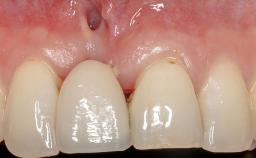

A 30-year-old woman was referred by her general dentist for evaluation of an esthetic complication related to previous implant treatment for congenitally missing maxillary lateral incisors. The patient’s chief complaint was the inadequate esthetic appearance of her smile. The case demonstrates the use of a combined approach to achieve optimal results. Two different flap designs - a tunnel technique and a coronally advanced flap - are employed based on the surgical objectives for the affected site.

Periodontal Plastic Surgery and Prosthetic Procedures to Treat Peri-Implant Soft-Tissue Dehiscences

Soft Tissue Grafting Yes

Soft Tissue Anatomy Intact Defective